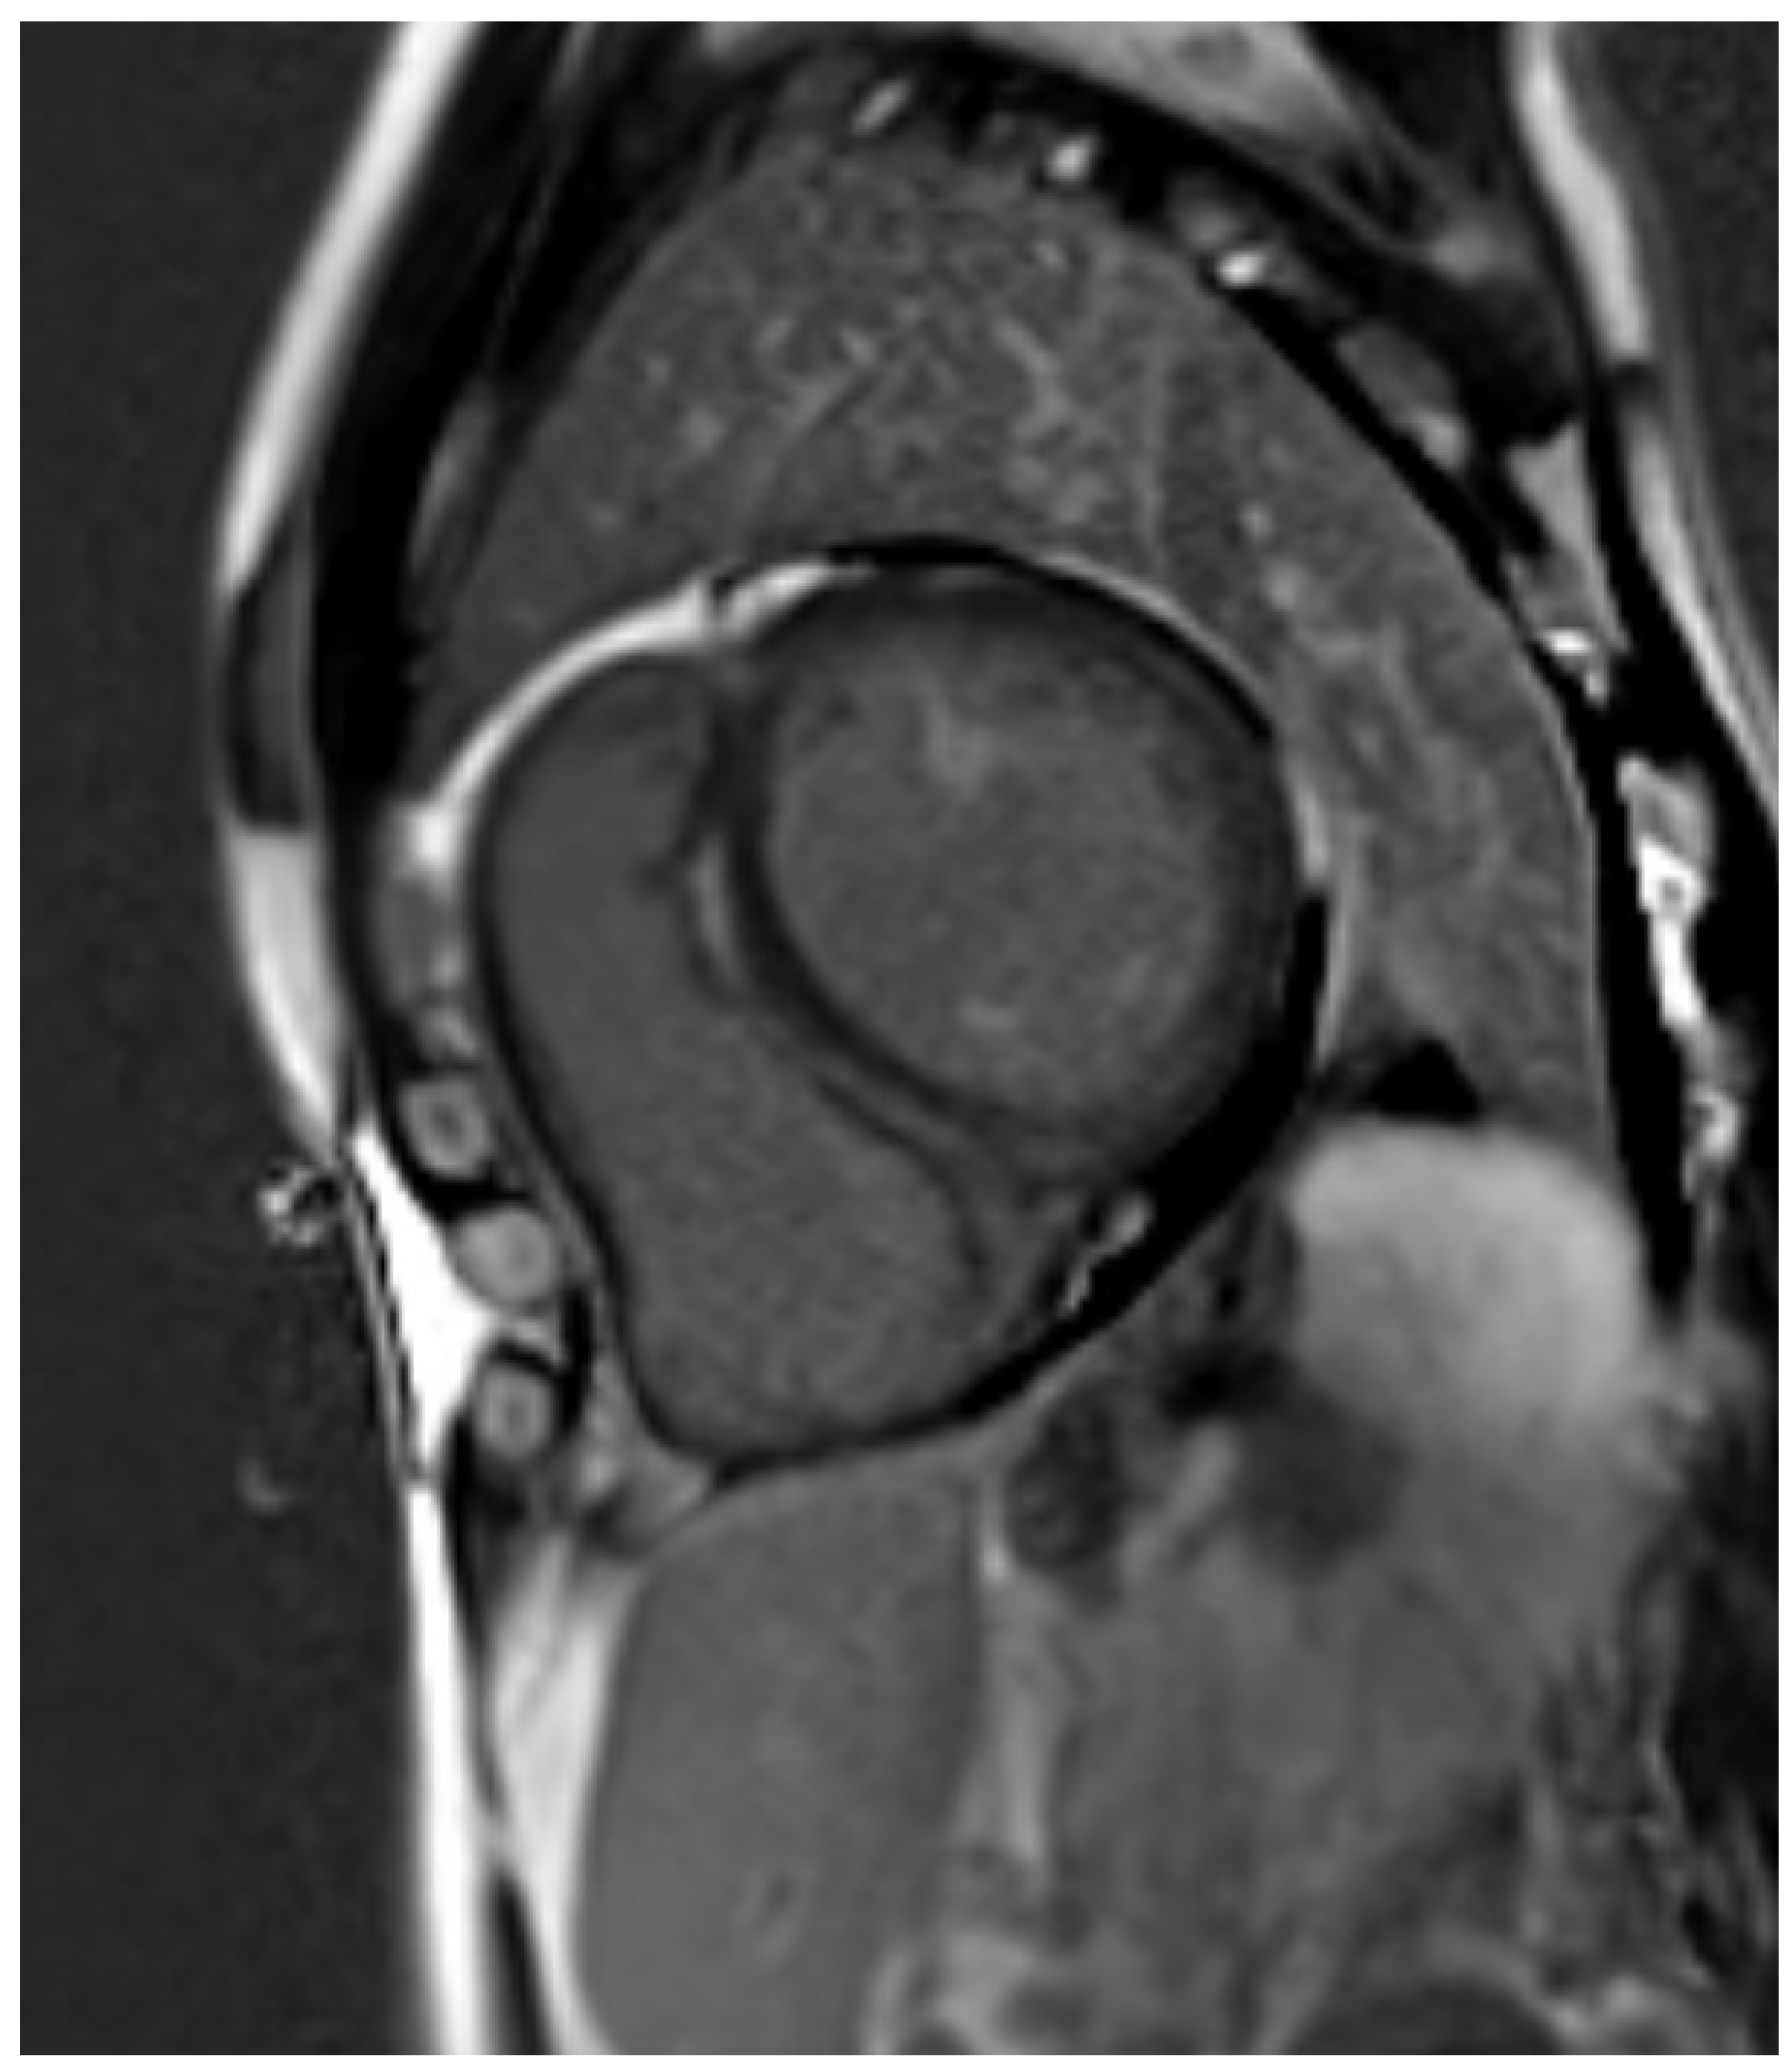

3.4. Hypertrophic Cardiomyopathy (HCM)

3.5. Fabry Disease